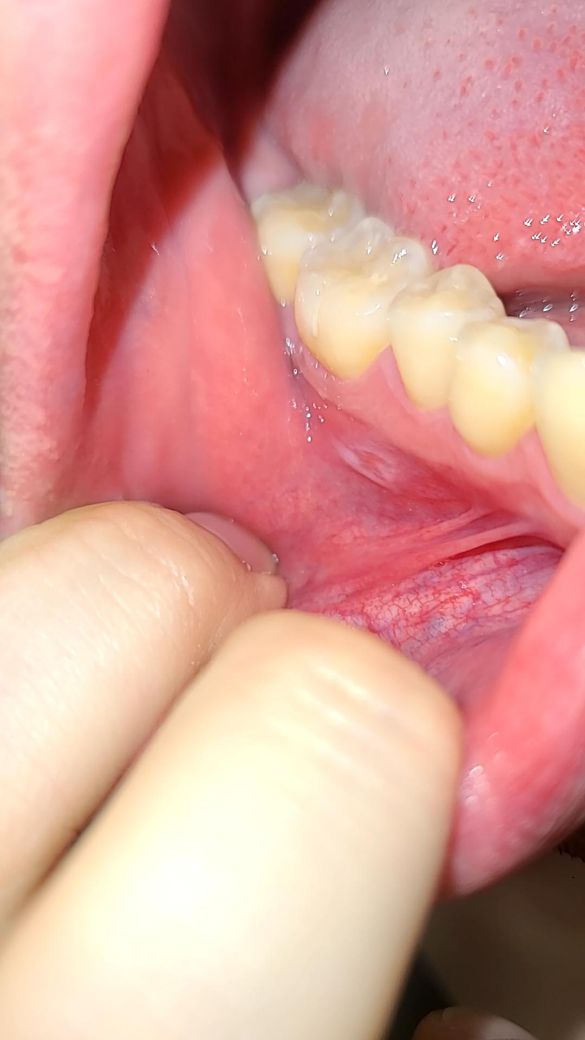

구내염 인지 뭔가가 좀 오래지속되는데요 구강암인가요

불편한지는 4주 정도 되었는데요

1주 더지나서 오늘 보니까 하얀게 보이네요

불편한건 더 심해졌어요

• 1번 째 사진

악성병소보다는 구내염에 가까운 것으로 사진상 보이는데요

오라메디 적용해보시고 호전되지 않으면 구강내과 가보세요